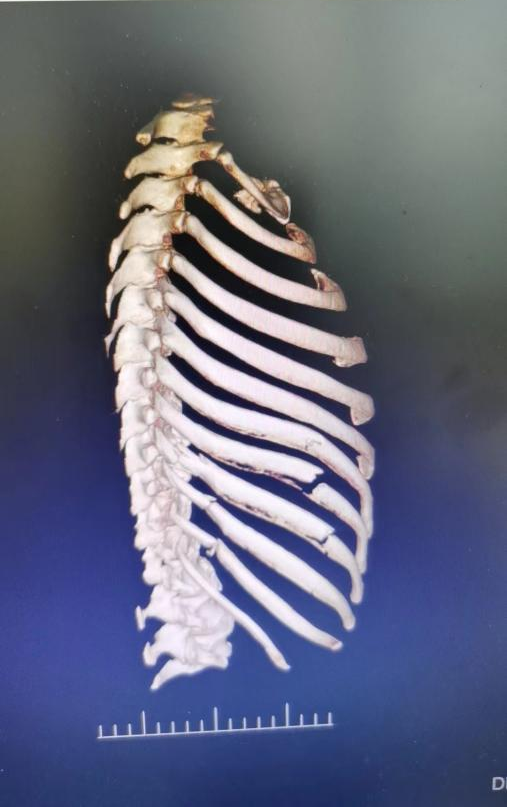

术中图片

肋骨结构肋骨共有12对,左右对称,连接胸椎和胸骨而组成胸廓,对胸部脏器起着保护作用。第1~3肋骨较短,且有锁骨、肩胛骨的保护,较少发生骨折;第4~7肋骨较长且固定,最易发生骨折;第8、9肋骨虽长,但借第七肋骨间接与胸骨相连而构成肋弓,弹性较大,不易折断;第11、12肋前缘游离,也称“浮肋”,较易避免暴力作用,不易骨折。